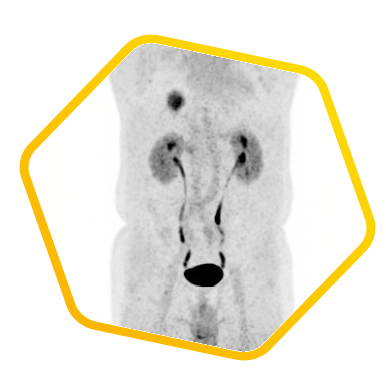

Dual tracer PET/CT (F-18 FDG and Ga-68 DOTATATE) are used for the metastatic evaluation of neuroendocrine tumor.

![]() [F-18] FDG |

![]() [Ga-68] DOTATATE |